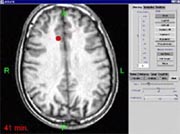

Online Imaging and Navigation Based

on the planning for access or for more complex therapy (e.g.

thermotherapy), the surgeon can now use interventional image data for

navigation in two complementary ways. One way is to update the complete

MRI volume at intervals. The other way is to select a specific

slice, using the tracked instrument currently in his hand. This slice is

then scanned by the MRI. Major disadvantages of

using the realtime slice image are the time needed to perform the scan

(2 - 5 seconds) and the poor image quality, in particular from MRI with

low field intensity (.2 or .5 Tesla).

On the left, see a realtime slice (.5 Tesla) and, on the right, the

corresponding image from a preoperative volume (3D sequence, .5 Tesla). The

LOCALITE iMRI Navigator lets the surgeon use specific vizualizations to

compare the realtime image and corresponding images from the planning

phase. When deviations are detected, the surgeon may acquire a current

iMRI volume and update the plan on its basis. This may be repeated as

necessary, leading to a process of iterative navigation. For the surgeon these

options are not mutually exclusive but complementary:

The right picture above connects to the planning results, while the

realtime slice on the left lets him evaluate the residual 'goodness' of

the planning data that are no longer up-to-date.